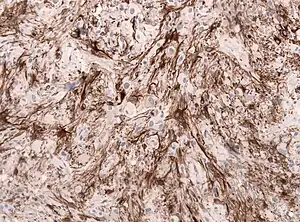

![]() | |

| GFAP stained microscopic section of a subependymal giant cell astrocytoma | |